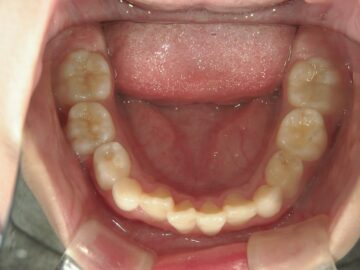

急速拡大装置で上顎の拡大が進むと、下顎の骨も調整する必要が出てきます。その際に使う装置がリンガルアーチです。下顎の骨は上顎の骨と作りが違います。下顎はひとつの骨で構成されているので、上顎と同じように拡大させることができません。内側に傾いている歯を起こすようにして歯列部分だけを拡げていきます。この装置も固定式の装置となっており、歯の裏側に装着しますので目立たない見た目となっています。